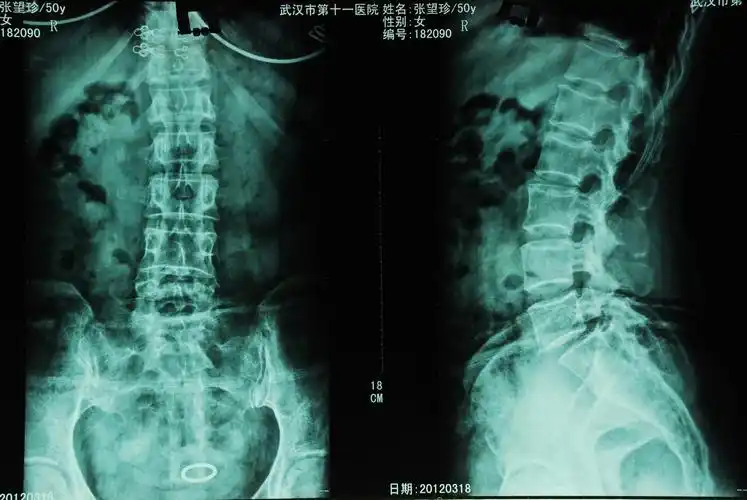

骶尾椎影像报告怎么写? - 知乎

附病例(x线 ct):另外,骶尾骨骨折,特别是尾椎脱位的诊断还要和临床

尾椎l5向后滑脱1/4 1度